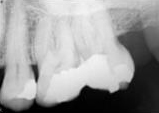

antes depois